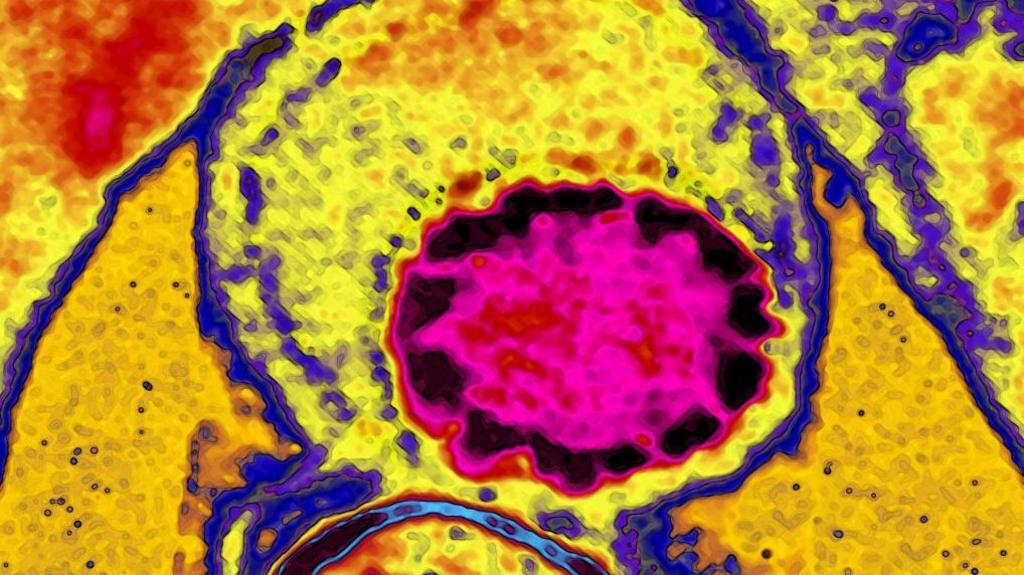

Vascular surgery involves complex procedures including angioplasty as shown in this CAT scan image showing an arterial stent